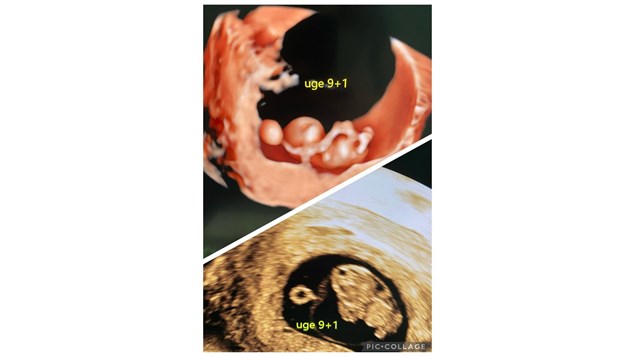

En af de nye verdensborgere der kommer til verden i begyndelsen af december 2024.

Det lille foster måler ca 25 mm. Hjerteslaget er ufattelige 186 slag/min

Alt ser fint ud, og den kommende mor gik glad fra klinikken.

Billeder i 2D og 3D.